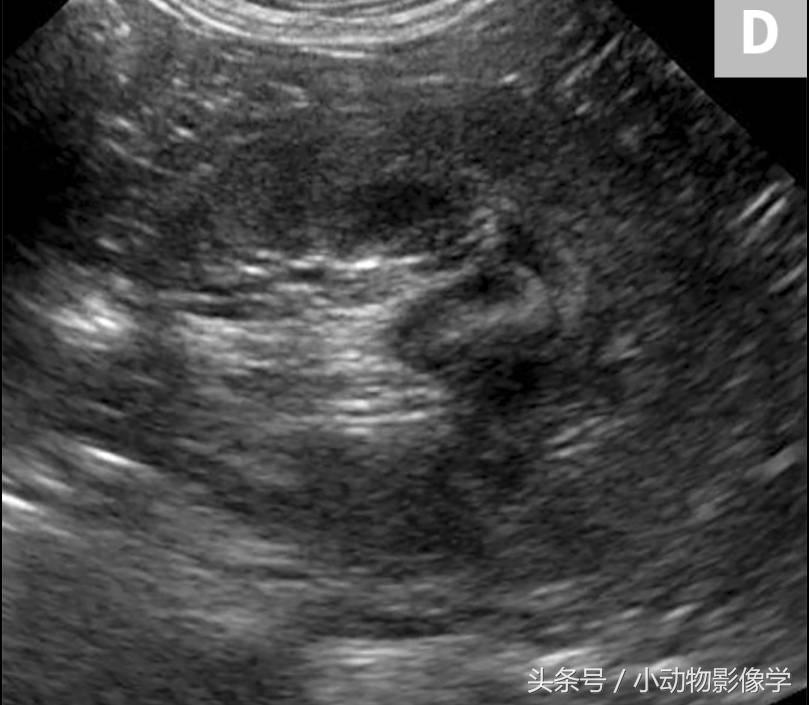

图1D、犬正常左肾中间部分的横截面图像。肾门(RH)和脉管系统可注意到沿肾内侧(图像左侧)。可以看到无回声的血管周围有大量高回声的脂肪。该图像是身体的“短轴”方向,左肾垂直于图1B和1C。